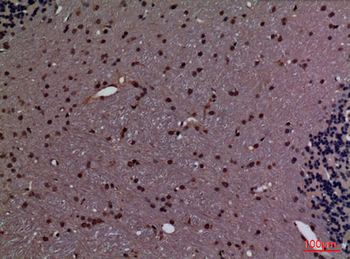

Anti-Cyclophilin A/PPIA Antibody [orb19174]

FC, ICC, IF, IHC, IHC-Fr, WB

Human, Mouse, Rat

Rabbit

Polyclonal

Unconjugated

10 μg, 100 μgCYPA Rabbit Polyclonal Antibody [orb100498]